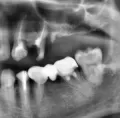

Отвалилась старая пломба, которую ставили девять лет назад. Пришел к стоматологу, она осмотрев сказала, что надо зачистить и заново запломбировать. Начав процедуру чистки, она попробовала пошатать зуб, потом сказала, что нужно сделать снимок. Снимок сделали, ее вердикт — надо удалять зуб, поскольку пошло воспаление вокруг корней, если его лечить со штифтами или еще как, через некоторое время он снова даст о себе знать и все равно придется удалить.

Есть ли смысл обратиться к другому специалисту? Или поверить и удалить?

Смысл конечно всегда есть, но если диагноз доктора подтвердится (воспаление на корнях), то скорее всего зуб придётся удалить.